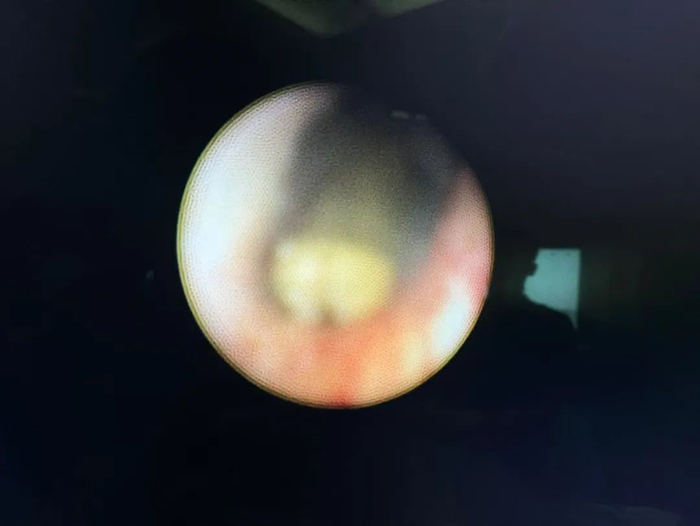

術(shù)中探查的精囊結(jié)石

精囊鏡探查手術(shù)過程順利,術(shù)中發(fā)現(xiàn)精囊內(nèi)有大量棉絮狀血塊及結(jié)石堵塞,啟動鈥激光將結(jié)石擊碎,疏通沖洗后通道通暢,術(shù)后予以抗感染對癥治療,患者康復(fù)出院。